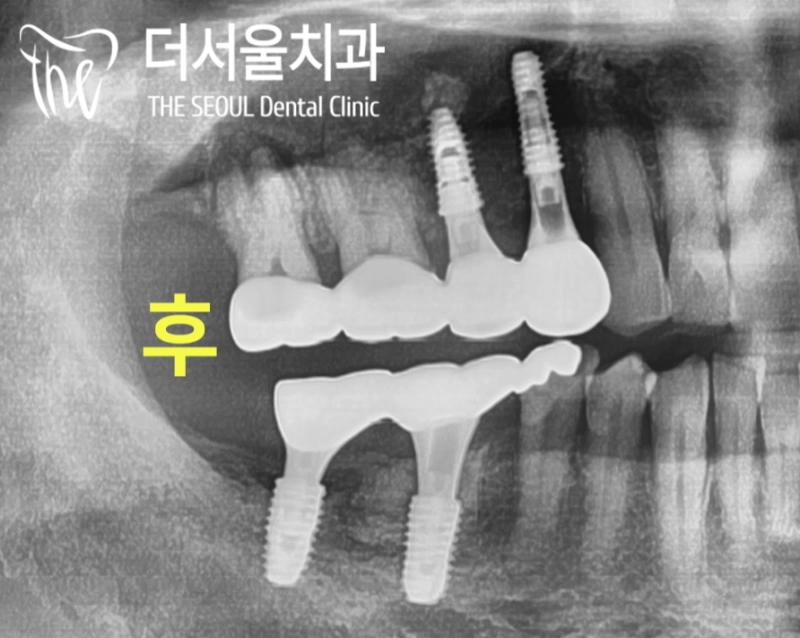

『# 14 # 15 # 46 implant

# 16 # 17 # 47 crown』

『진료 과정』

디지털 방식의 분석을 이용하여

식립 방향 및 각도를 결정하고

최종적으로 심어질 위치까지 선정했습니다.

이후 계산된 곳에 튼튼한 픽스처를 심어드렸죠.

몇 달간 기존 조직과 잘 어우러질 수 있도록

회복 기간을 부여하기로 했습니다^^

다른 곳들의 진료도 함께 진행했는데요.

썩어있는 곳을 확실하게 제거한 뒤

크라운 제작을 통해 외형, 기능을 잡았습니다.

# 47은 심어져있던 픽스쳐 위에

크라운을 올려드려야 되는 과정이라

어려움이 있었는데요.

.

# 47 기존 크라운 제거

방사선 엑스레이 촬영으로

제품명과 사이즈를 판독한 뒤

관련 부품을 수급하여

# 46 크라운을 올릴 때 같이 해드렸습니다.

( 성남치과 에는 안 되는 것이 없죠^^)

『마무리』

모든 보철이 완성되었습니다.

흔들리던 크라운은 물론이며

염증이 생겨 있던 곳까지

튼튼한 보철로 채워져 있는데요.

정말 자연스럽게 구강 내에

자리를 잡고 있는 크라운들이 확인되었습니다.